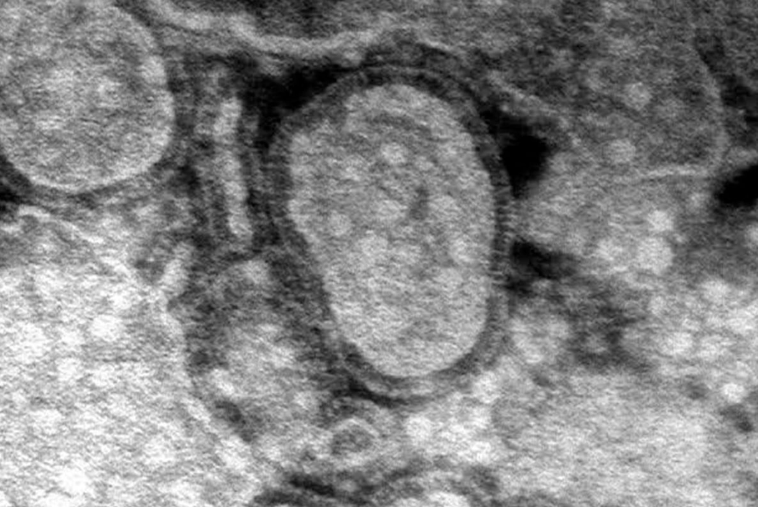

Cinco años después de la pandemia de Covid-19, China enfrenta un brote de metapneumovirus humano (HMPV), otra enfermedad respiratoria. Según informes y publicaciones en redes sociales, el virus se está propagando rápidamente y algunos afirman que los hospitales y crematorios están desbordados. Videos compartidos en línea muestran hospitales abarrotados, y algunos usuarios indican que múltiples virus, como la influenza A, el HMPV, Mycoplasma pneumoniae y Covid-19, están en circulación.

Se ha especulado que China ha declarado el estado de emergencia, aunque esta información no ha sido confirmada. Se sabe que el HMPV causa síntomas similares a los de la gripe y puede generar signos parecidos a los del Covid-19. Los funcionarios de salud están siguiendo de cerca la situación mientras el virus continúa propagándose.

Los casos recientes incluyen patógenos como el rinovirus y el metapneumovirus humano, con un aumento notable en los casos de HMPV entre niños menores de 14 años, especialmente en la región de Uttar Pradesh.